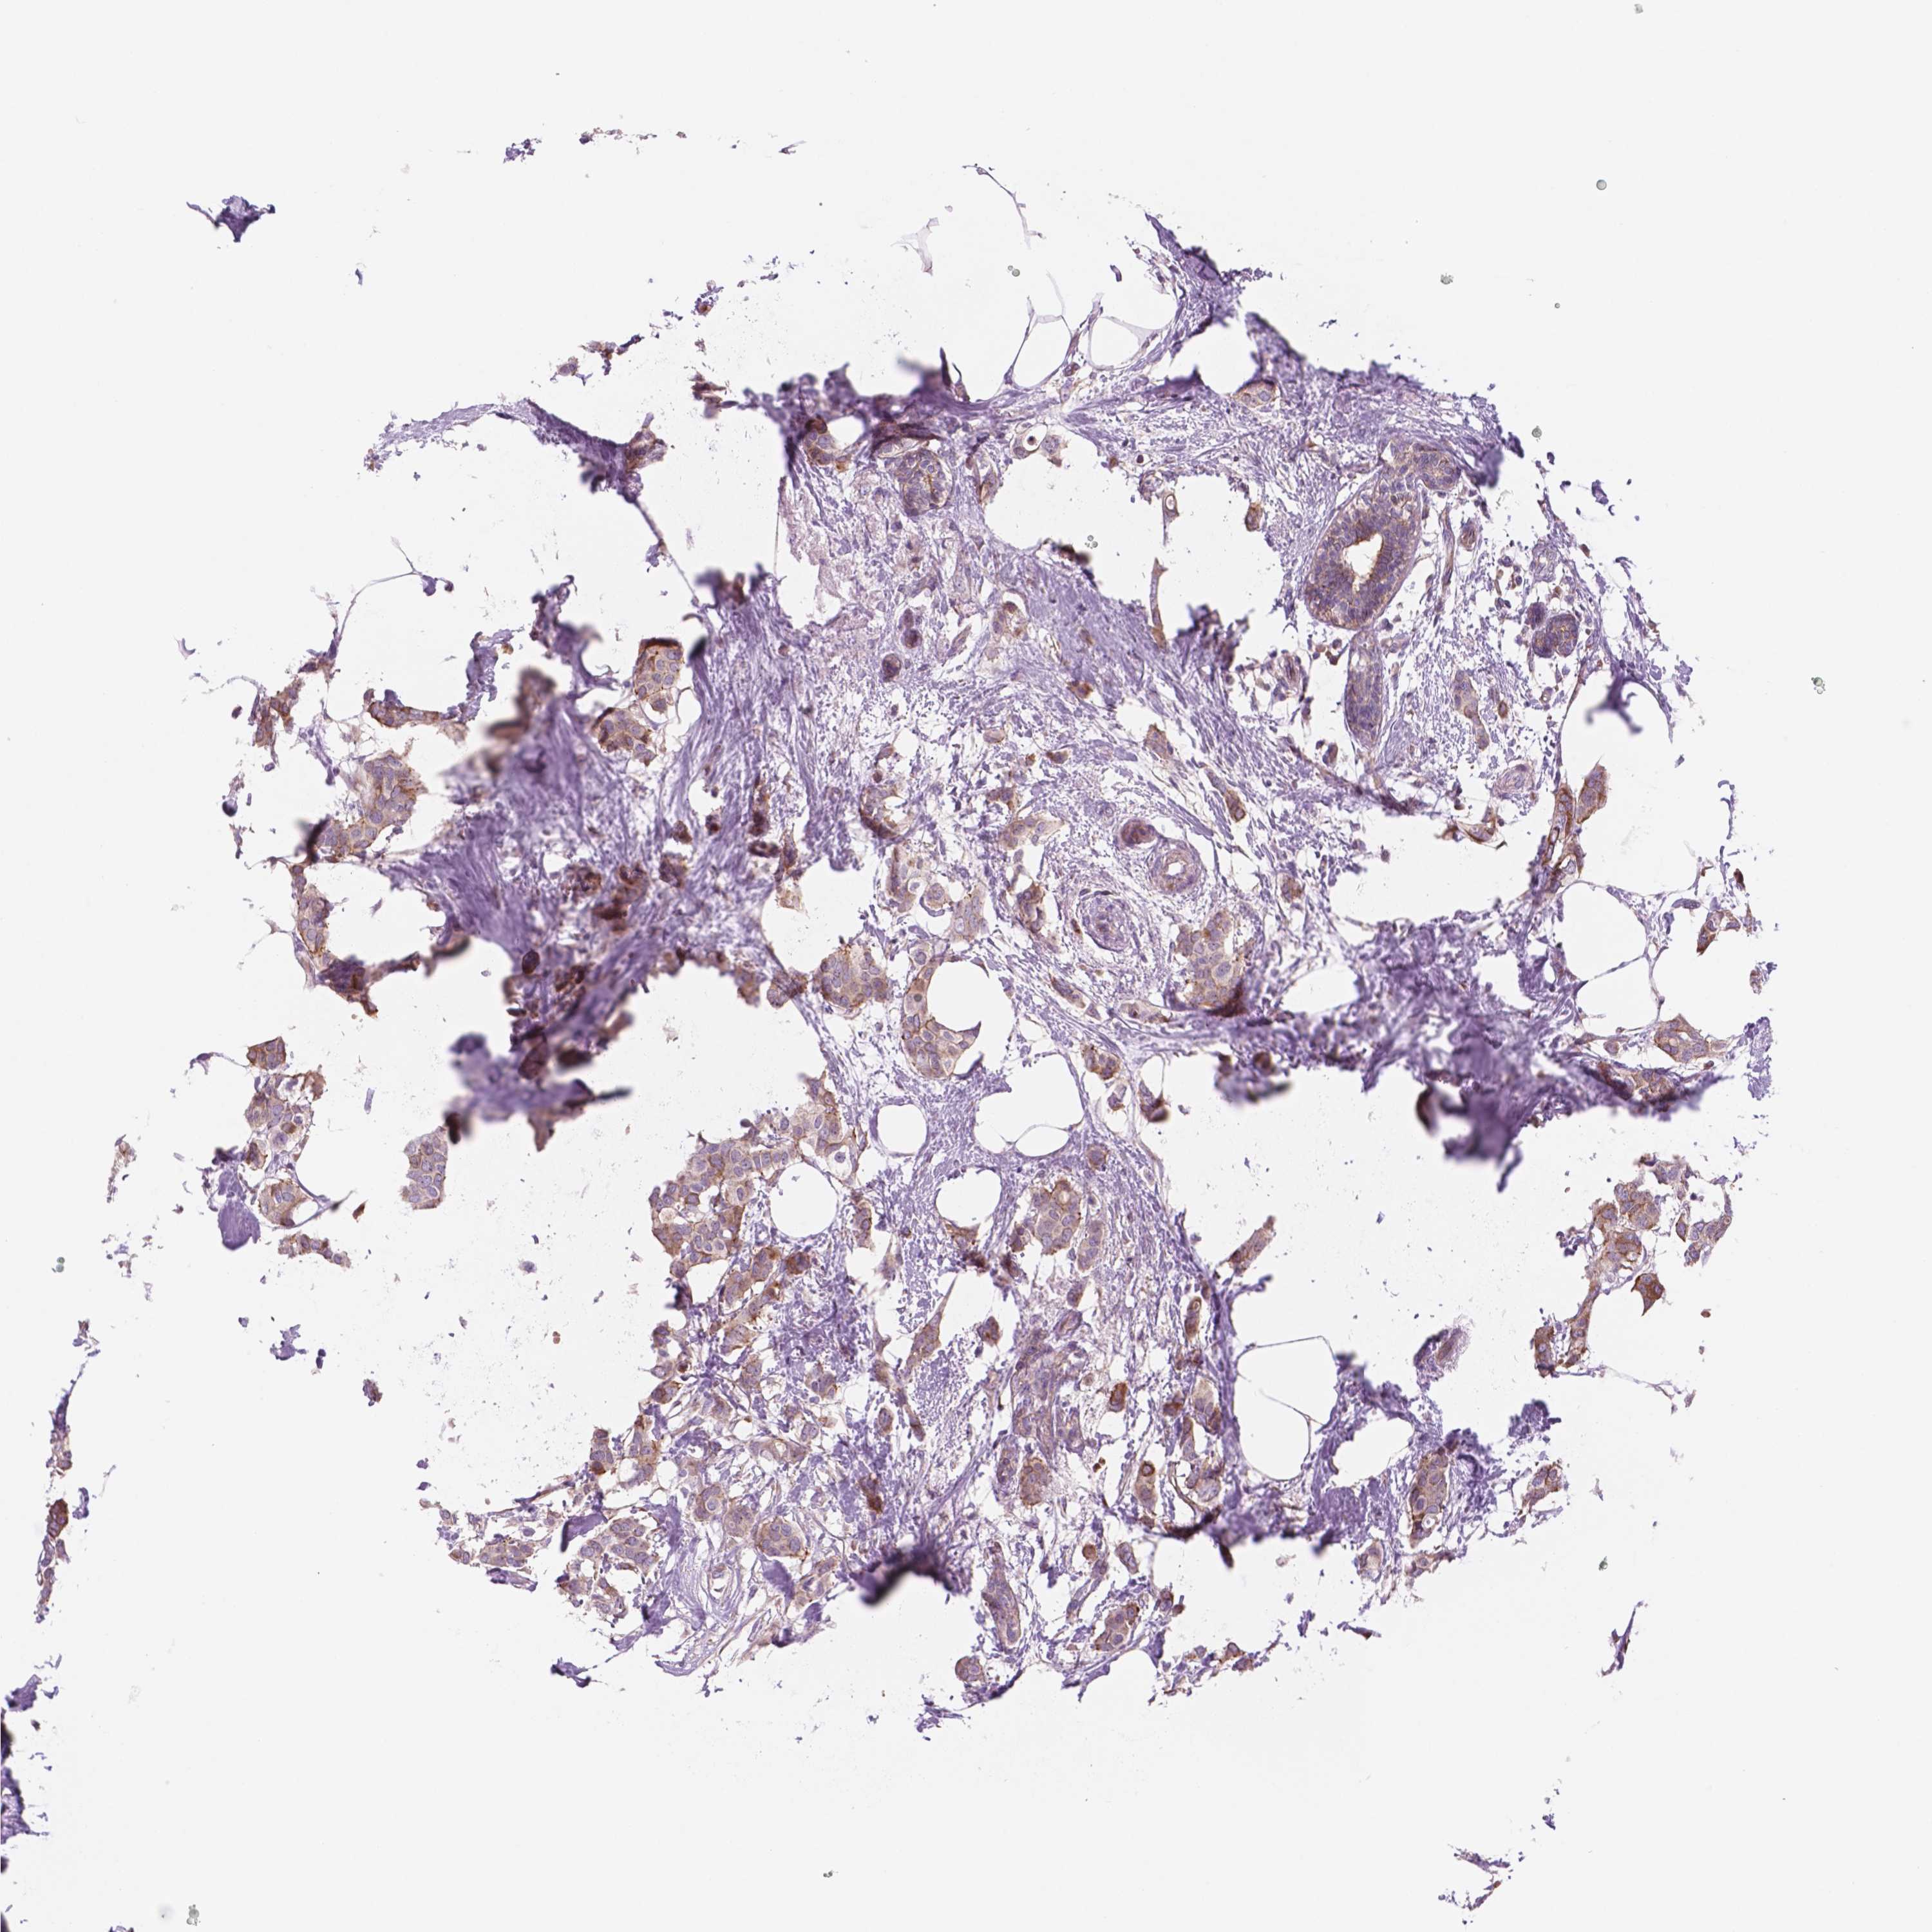

CANCER BREAST CANCER Show tissue menu

Breast cancer

Human cancer